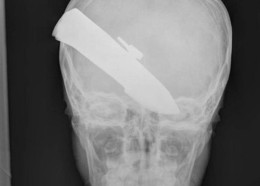

Чудни ренгенски снимки

Фото на денот #630